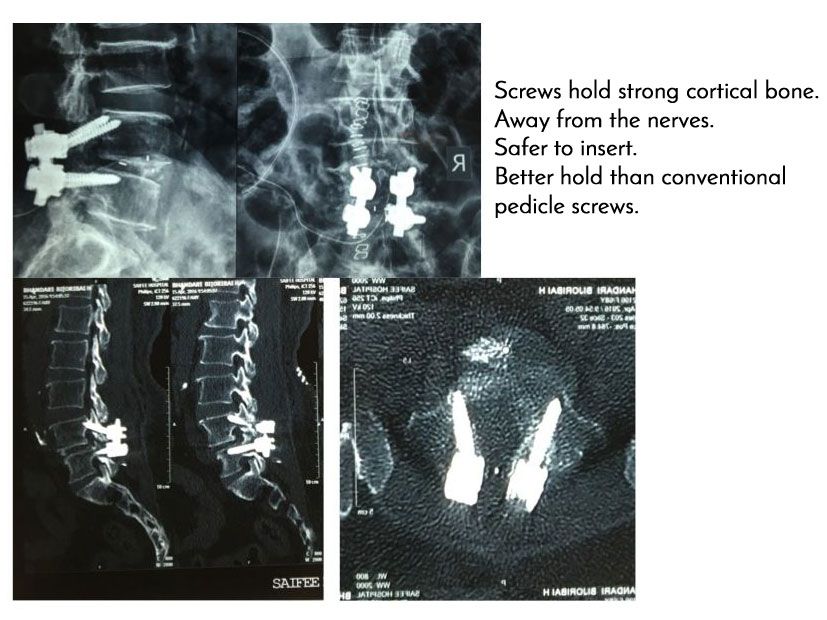

New technique for inserting screws in osteoporotic patients